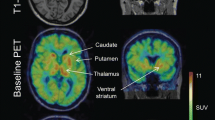

The mean age and weight of the study sample (n = 12 men) were 33 ± 8 years and 72 ± 13 kg, respectively. The regional brain mGluR5 availability in this sample was in agreement with the known distribution of mGluR5 in humans, with highest availability in the cingulate cortex (anterior and posterior), striatum and prefrontal regions and lowest availability in cerebellum and pons (Fig. 4). Then it decreased slowly and linearly until the end of the acquisition. We obtained good quality MR spectra from all subjects allowing reliable quantification. The mean glutamate and glutamine levels in the ACC were 5.84 ± 0.64 and 3.40 ± 0.93, respectively. Then, metabolites were quantified relative to creatine (Cr) and the mean Glu/Cr, Gln/Cr, and Glx/Cr levels were 1.12 ± 0.12, 0.64 ± 0.14, and 1.75 ± 0.18, respectively (Fig. 5). To test for an interaction of mGluR5 density and glutamate concentration, we correlated the [18F]FPEB BPND with Glu/Cr, Gln/Cr, and Glx/Cr ratios in the ACC. In the whole sample, ACC BPND did not correlated with ACC glutamate (r = 0.51; p = 0.09), glutamine (r = −0.46; p = 0.13) or Glx (r = −0.035; p = 0.92) (Fig. 5).